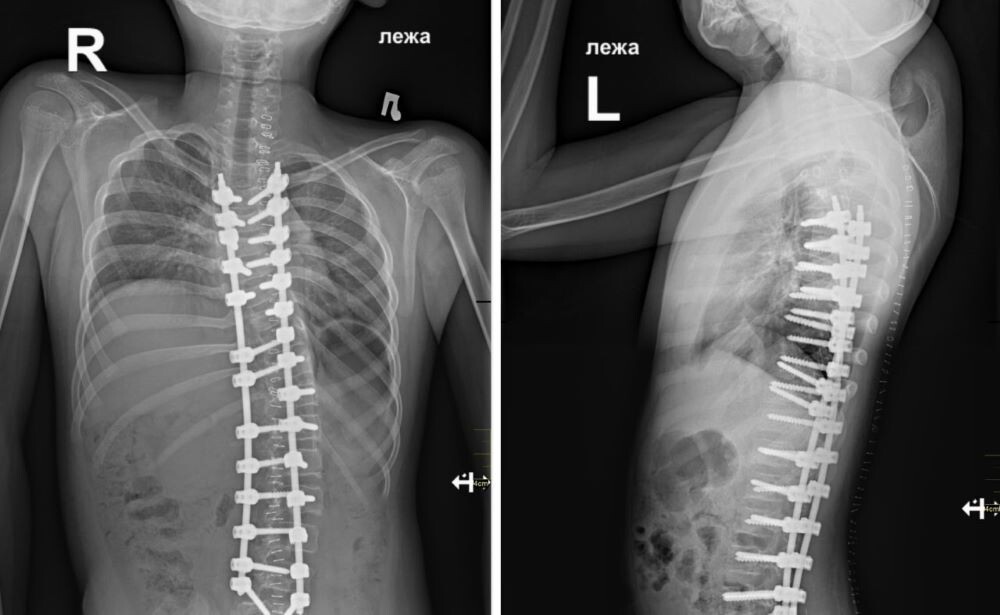

Деформации позвоночника достигла критических значений – более 140 градусов искривления, без операции в дальнейшем мальчик не смог бы даже сидеть. Операция длилась четыре часа, была проведена тотальная фиксация позвоночника от груди до поясницы, установлена специальная металлоконструкция. Деформацию удалось скорректировать до 32 градусов – это обеспечит мальчику комфортную жизнь. Сейчас юный пациент выписан и будет восстанавливаться дома.

Фото: Новосибирский НИИТО имени Я.Л. Цивьяна